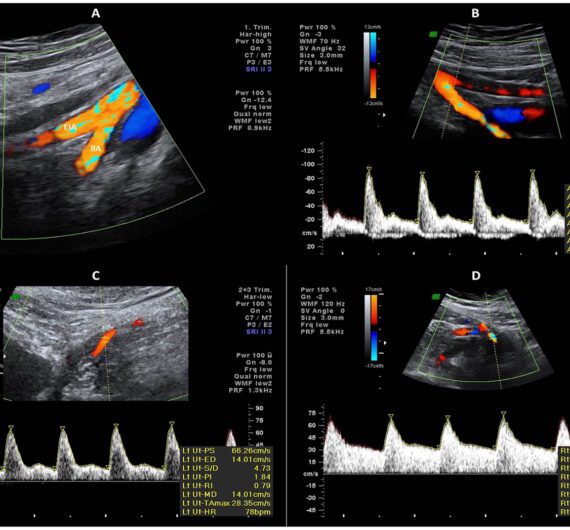

Ultrassom com Doppler Colorido de Aorta E Artérias Renais

Ultrassom com Doppler Colorido de Aorta E Iliacas

Ultrassom com Doppler Arterial de Membro Inferior Direito (A-MID)

Ultrassom com Doppler Arterial de Membro Inferior Esquerdo (A-MIE)